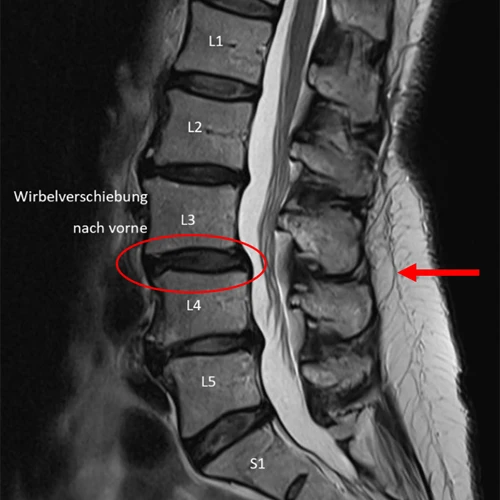

1. Beispiel – Wirbelverschiebung nach vorne

Vergleicht man die Messung der Medi Mouse mit der MRI-Aufnahme der Lendenwirbelsäule der gleichen Patientin, kann man erkennen, dass die Höhe der Knickstellung, welche ihre Ursache in der Wirbelverschiebung nach vorne hat, beim gleichen Segment detektiert wurde.